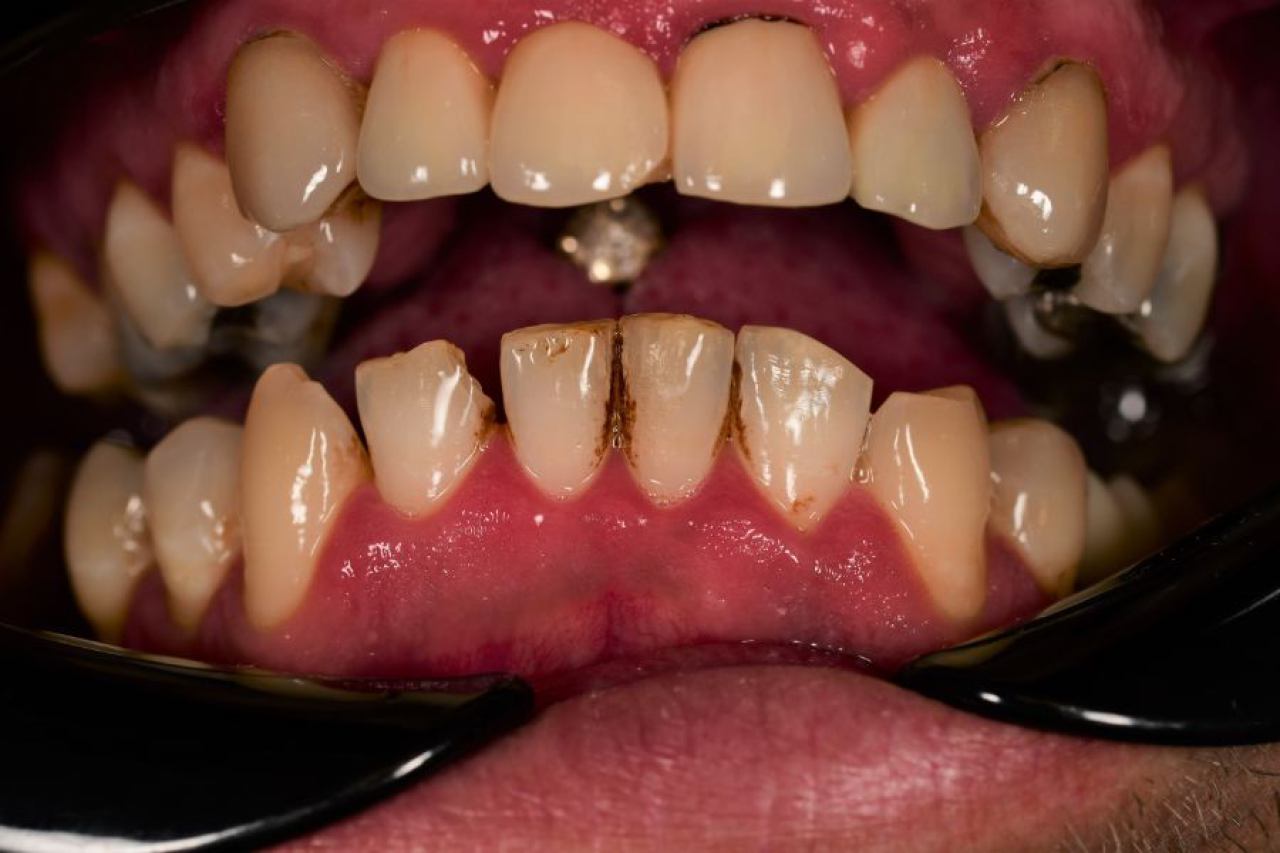

Parodontologija i kirurgija

Parodontologija je grana dentalne medicine koja se bavi zdravljem potpornih struktura zuba (parodonta). Parodont se sastoji od zubnog mesa (gingiva), kosti i vlakana koja vežu zub za kost (parodontalni ligament).

Ovo je grana kojoj Marković Dental Clinic pridaje puno pažnje jer je vrlo kompleksna i bitna za cijelo oralno zdravlje.